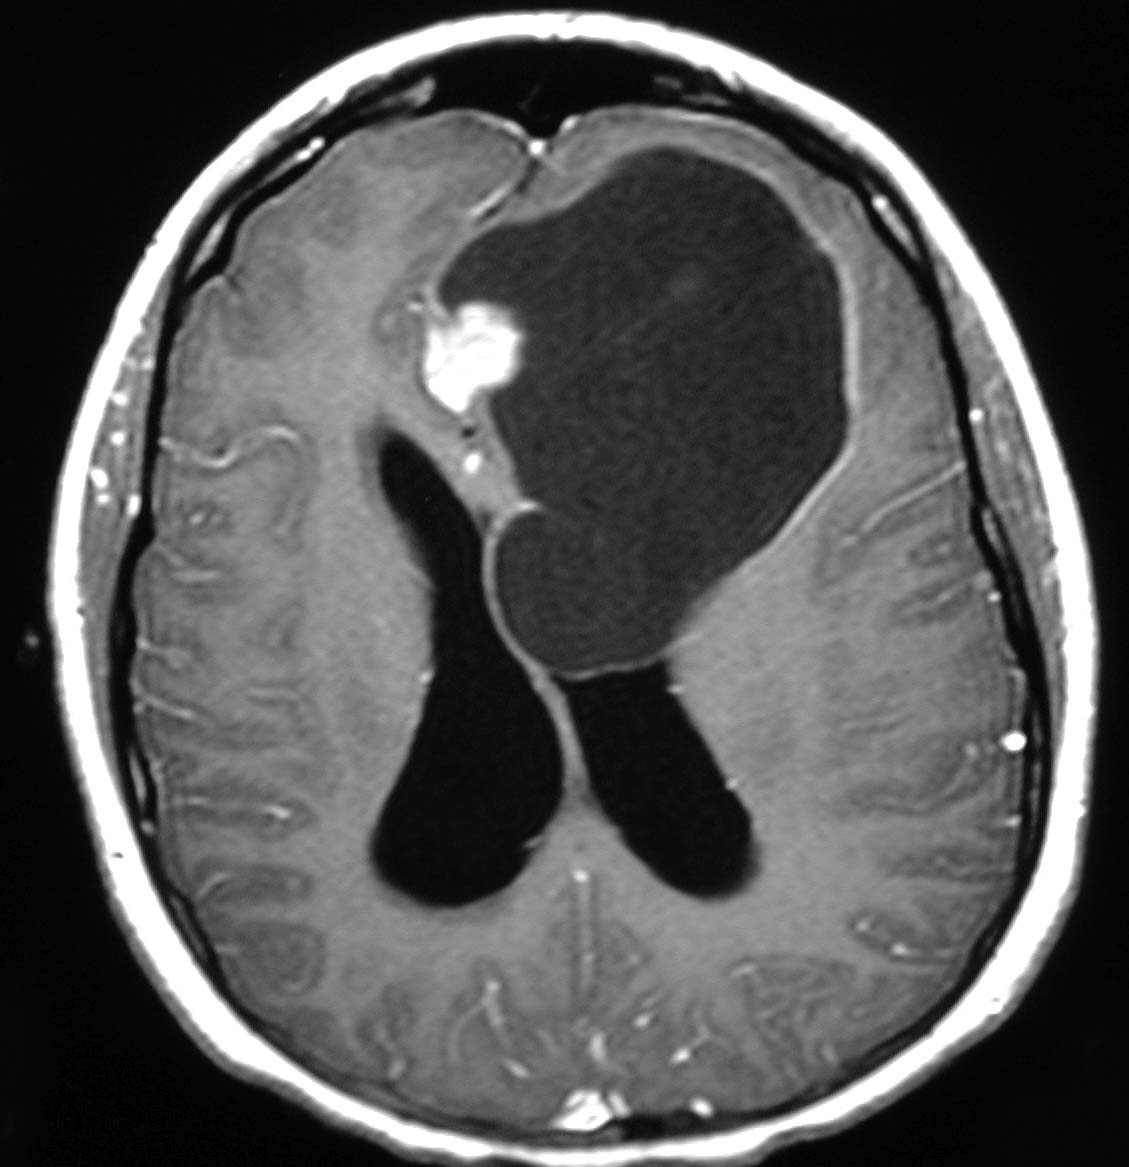

Most brain and spinal tumours are diagnosed with a CT scan or an MRI. Often doctors order a CT scan when the child presents to the emergency room. A CT scan is an easier type of brain scan to arrange and most often doesn’t need sedation. When a brain tumour is suspected or found, an MRI will most likely follow. This MRI will require the child to lie perfectly still, so depending on the age and maturity of the child, sedation may be required. For most tumours a dye will be injected into your child’s intravenous (IV) part way through the MRI to enhance or highlight certain features of the tumour and guide us in deciding what type of tumour it is and the next steps in treatment. Most children will also require some blood work at the same time to check how healthy they are and to prepare them for treatment such as surgery. When we suspect certain types of tumours, we may order very specific blood work such as alpha-fetoprotein (AFP) or beta human chorionic gonadotropin (beta-H_ C_ G_). These “markers” or indicators can help us identify what type of tumour you child has.

MRI of brain tumour